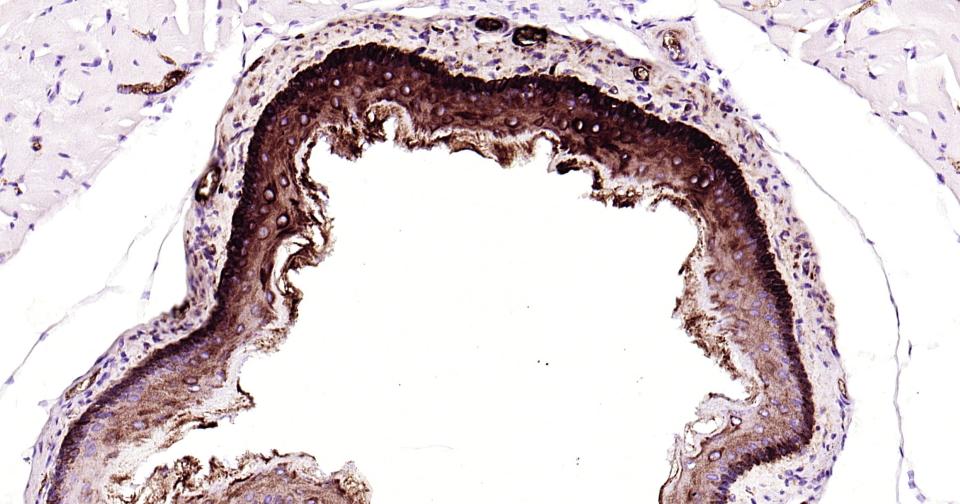

Paraformaldehyde-fixed, paraffin embedded Human Esophagus; Antigen retrieval by boiling in sodium citrate buffer (pH6.0) for 15 min; Antibody incubation with Cytokeratin 14? Monoclonal Antibody, Unconjugated(bsm-52054R) at 1:200 overnight at 4°C, followed by conjugation to the bs-0295G-HRP and DAB (C-0010) staining.

Paraformaldehyde-fixed, paraffin embedded Rat Esophagus; Antigen retrieval by boiling in sodium citrate buffer (pH6.0) for 15 min; Antibody incubation with Cytokeratin 14? Monoclonal Antibody, Unconjugated(bsm-52054R) at 1:200 overnight at 4°C, followed by conjugation to the bs-0295G-HRP and DAB (C-0010) staining.

Paraformaldehyde-fixed, paraffin embedded Mouse Esophagus; Antigen retrieval by boiling in sodium citrate buffer (pH6.0) for 15 min; Antibody incubation with Cytokeratin 14? Monoclonal Antibody, Unconjugated(bsm-52054R) at 1:200 overnight at 4°C, followed by conjugation to the bs-0295G-HRP and DAB (C-0010) staining.